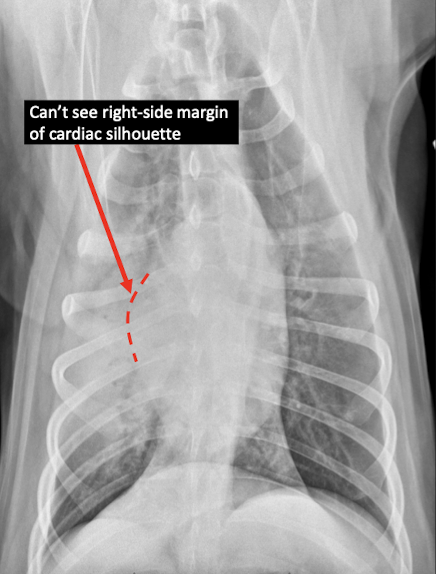

Q

Lung Pattern?

A

Alveolar

Border effacement

What is the appearance of border effacement?

Lose visibility of margins of cardiac silhouette, diaphragm, etc.